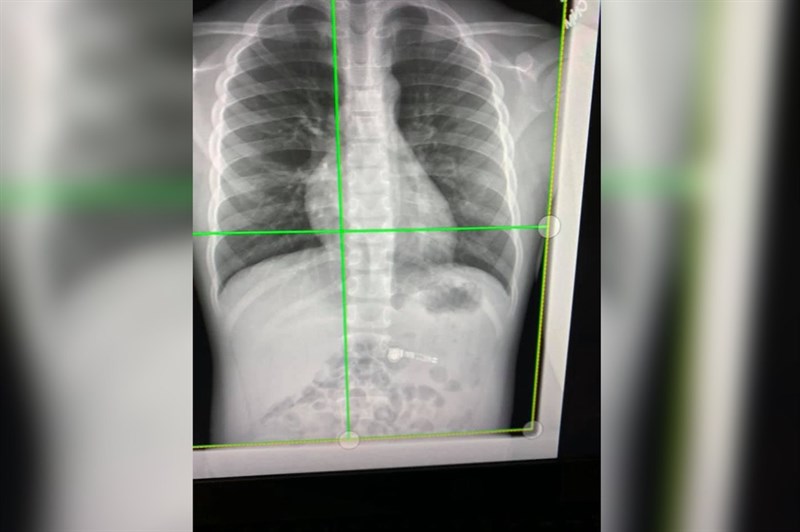

Uống thuốc là một hoạt động bình thường của con người, nhưng để xảy ra sự cố này thì quá thật là quá bất cẩn. Mặc dù tài khoản TikTok @iamcarliiib nói rằng cô ấy đã đi chụp X-quang để xác nhận điều đó. Và cô ấy cho biết sẽ không cố gắng sử dụng tai nghe này của mình nữa.

Trong một video khác được cô này đăng tải, người phụ nữ cũng tiết lộ rằng AirPods bị nuốt chửng vẫn đang được kết nối với điện thoại iPhone của cô ấy khi cô ấy thực hiện cuộc gọi. Trong một bản ghi âm được người phụ nữ này gửi cho bạn của mình, phát ra những tiếng ọc ọc từ bên trong bụng của cô ấy.